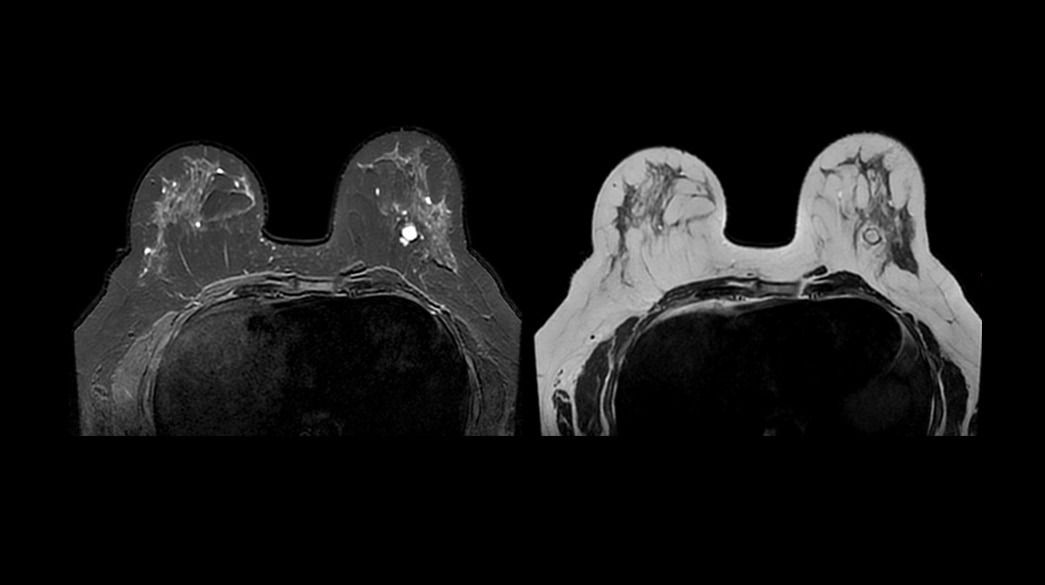

<p>AIR Recon DL</p>

Learn more ico-caret-right